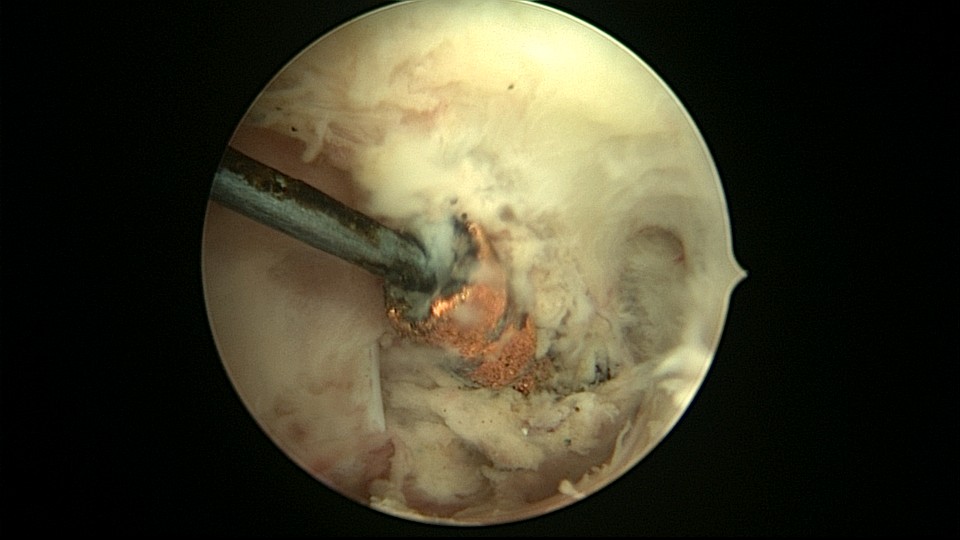

患者48岁,G3P1,顺产1次。安环10年,绝经1年,外院取环失败,子宫穿孔,腹部平片无异常。宫腔镜见宫腔广泛致密粘连,V型环与粘连组织嵌顿,取环钩盲视下多次尝试钩取节育环,均失败。取环钩循镜鞘外侧进入宫腔,直视下钩住节育环,顺利取出。再次置镜寻找子宫穿孔处并进入盆腔,见网膜脂肪组织,确认无活动性出血及盆腔积血,结束手术。